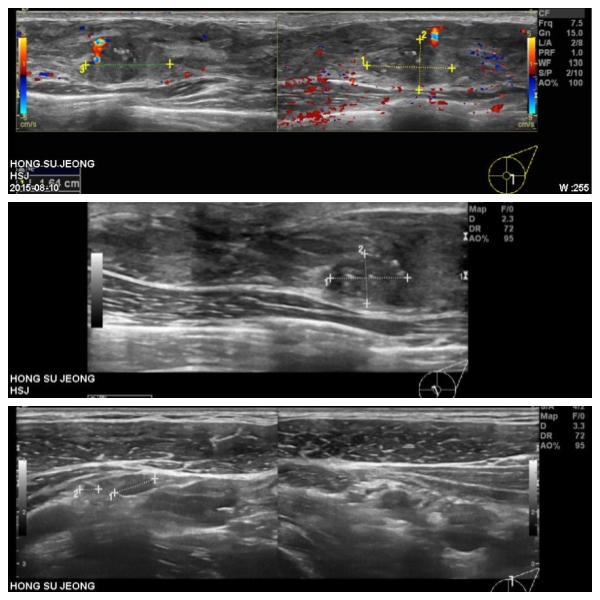

좌측에 만저지는 몽우리로 내원하신 30대 여성분으로 본원에서 유방 초음파 시행 하였으며  좌측 5~6시 방향있는 의심 스러운 혹 조직검사와 좌측 겨드랑이 림프절 비대 세포검사시행하여 좌측 침윤성 유관암과, 림프절 전이 진단 되었습니다.